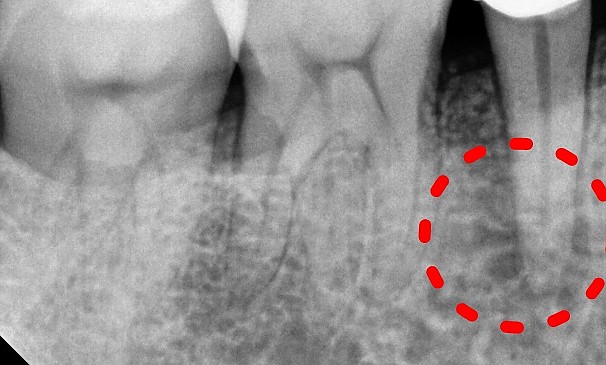

임OO님 전후사진 | 치료 기간 : 1주

치료 전

치료 후